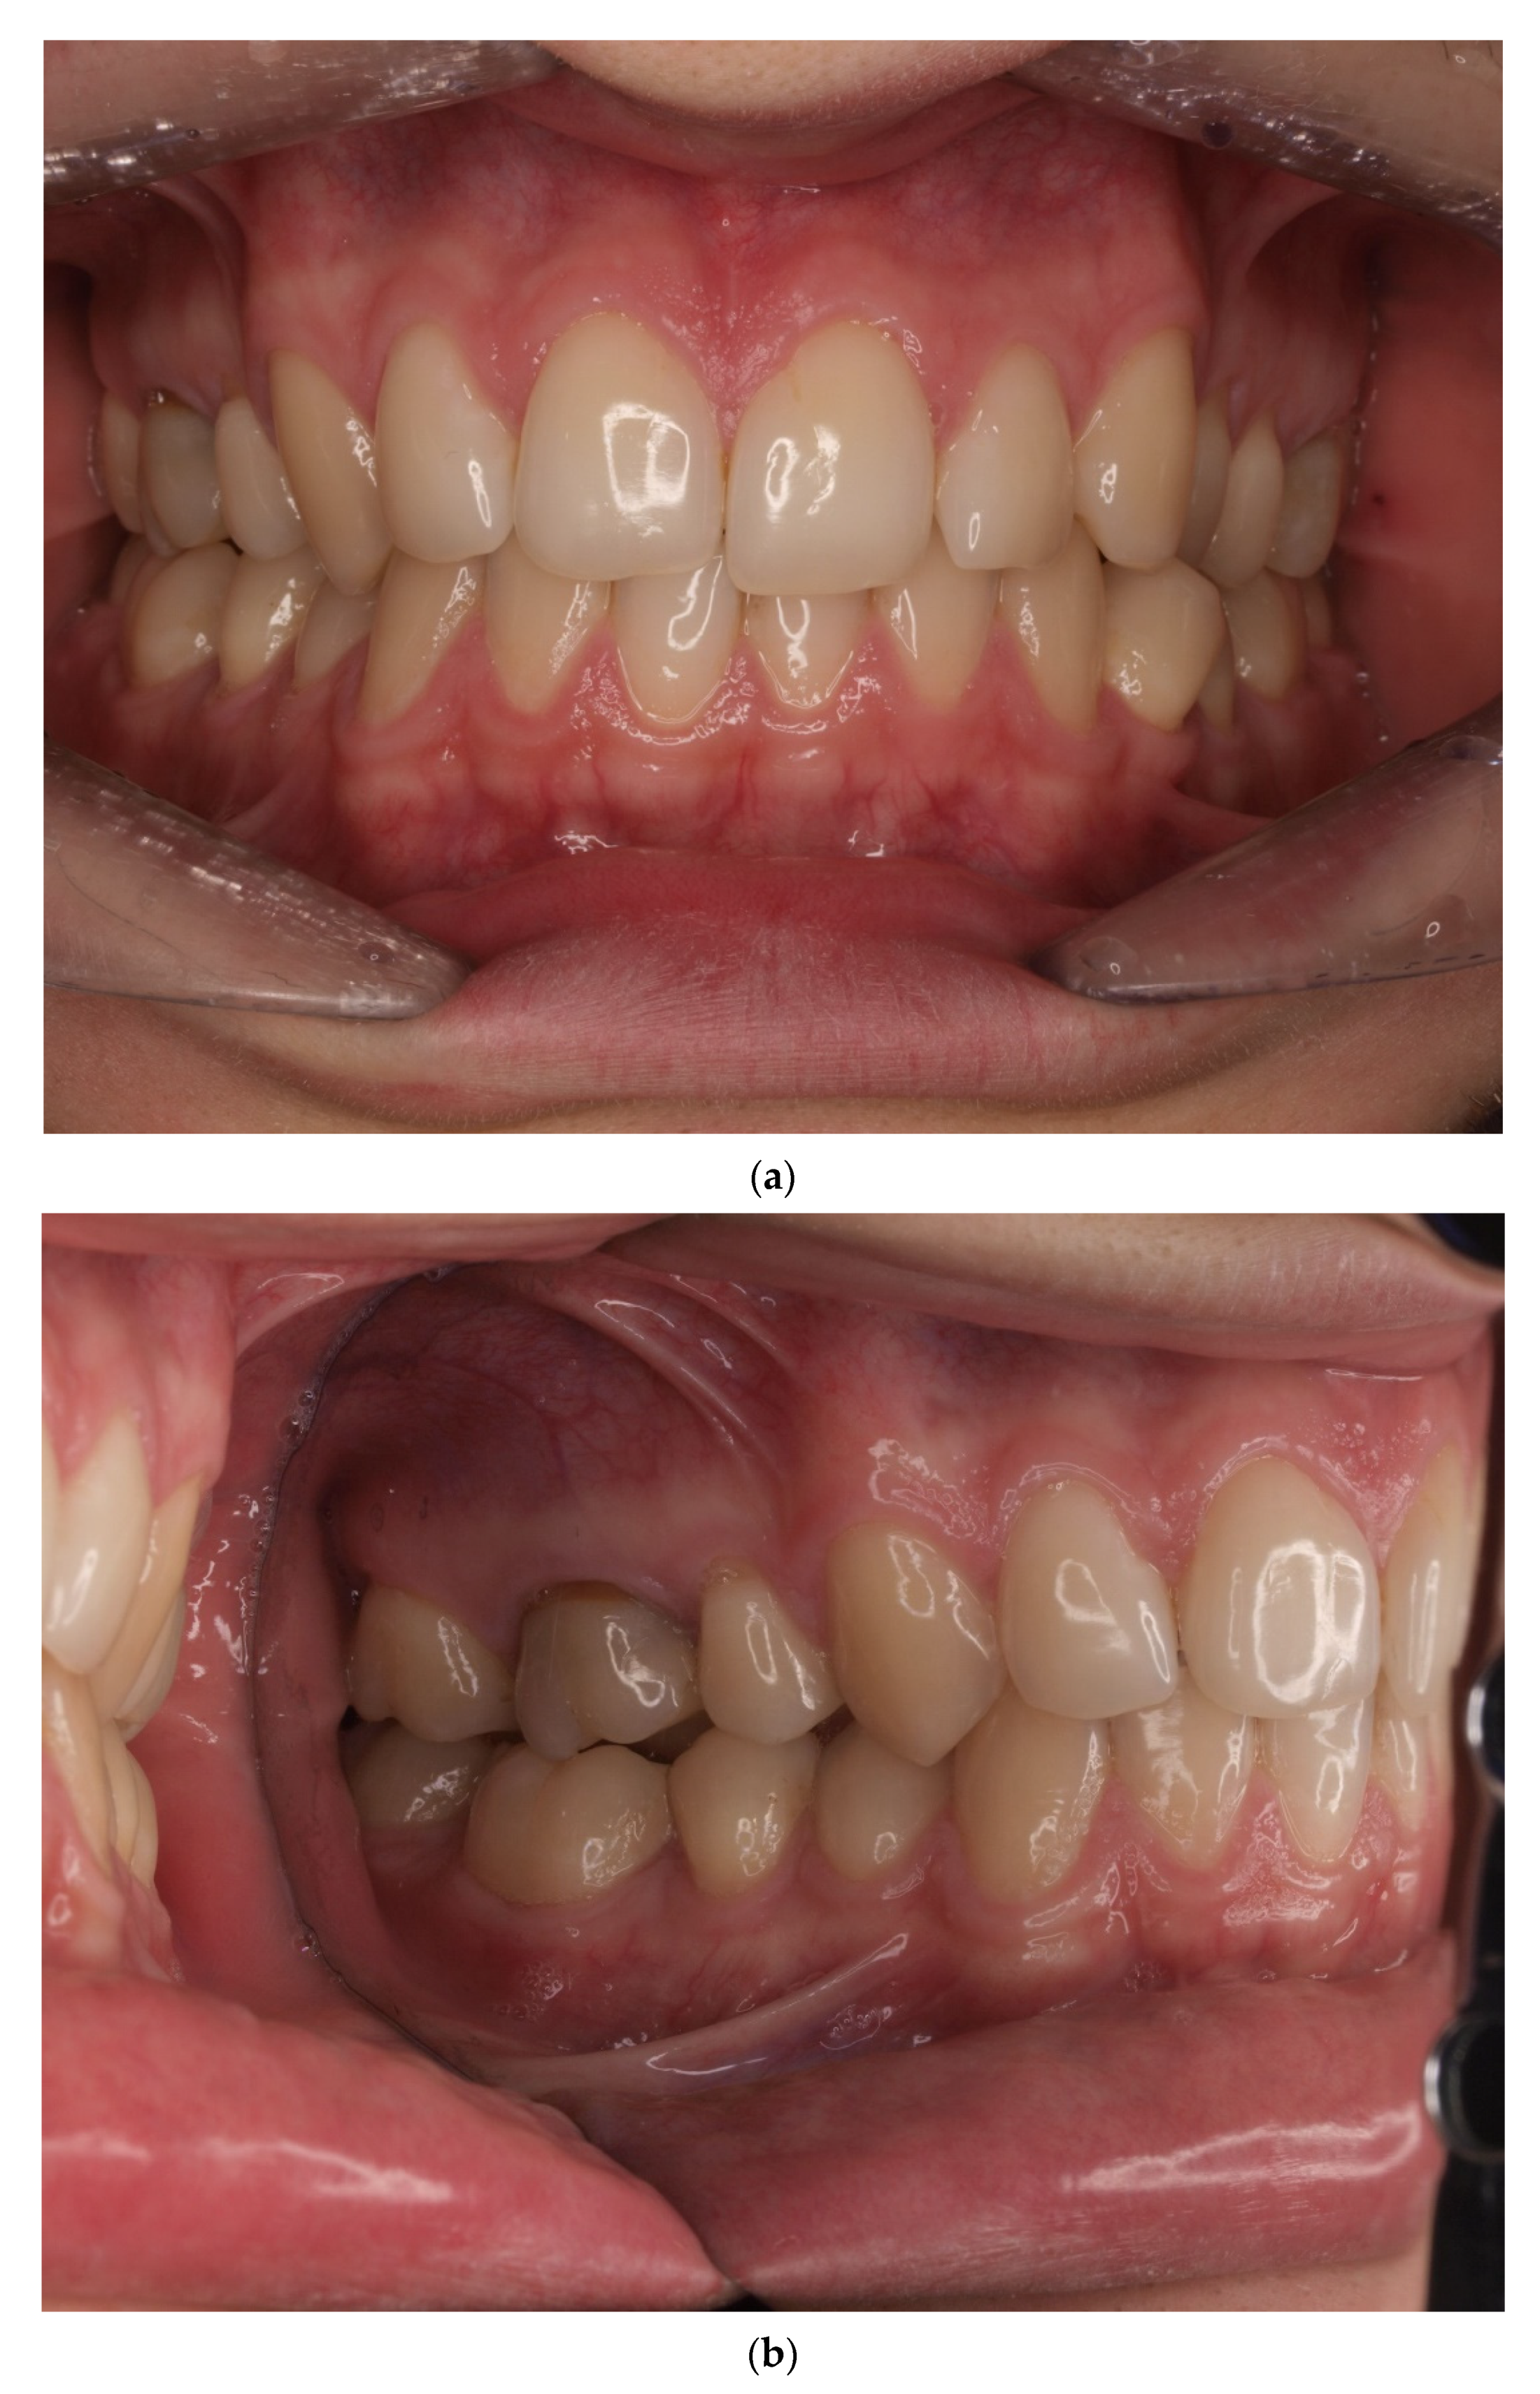

2. Materials and Methods

4. Results

- Sulewska, M.; Duraj, E.; Bugała- Musiatowicz, B.; Waszkiewicz -Sewastianik, E.; Milewski, R.; Pietruski, J.; Sajewicz, E.; Pietruska, M. Assesment of the effect of the corticotomy-Assisted orthodontic treatment on the maxillary periodontal tissue in patients with malocclusions with transverse maxillary deficiency: A case series. BMC Oral Health 2018, 18, 162. [Google Scholar] [CrossRef]